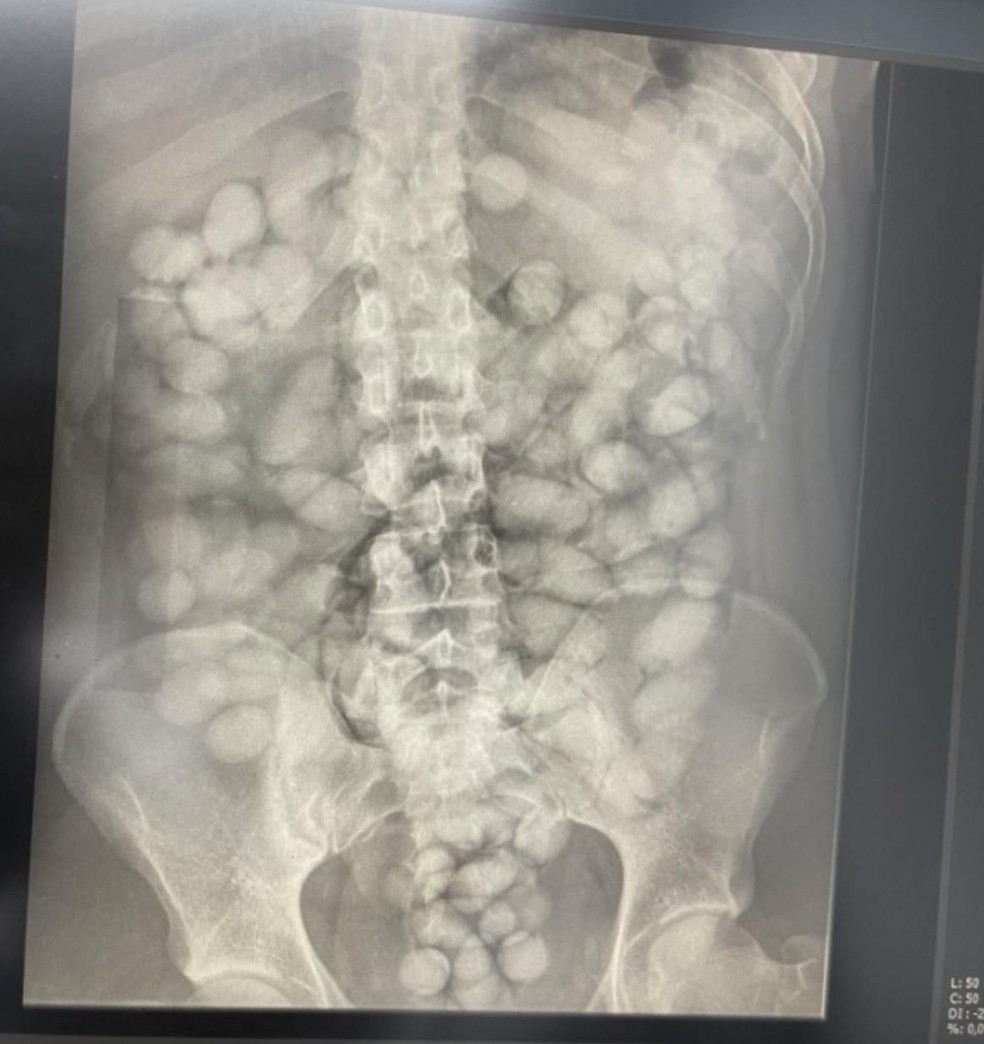

Segundo a investigação, grupo recrutava viajantes para levar cocaína em cápsulas ingeridas.

Segundo a investigação, grupo recrutava viajantes para levar cocaína à Europa em cápsulas ingeridas. — Foto: Polícia Federal

A ação faz parte da operação Nexus Aliciae, que começou após uma prisão em flagrante realizada no Aeroporto de Viracopos, em setembro de 2023. Na ocasião, uma mulher foi presa tentando embarcar para Paris com 563 gramas de cocaína ingeridas em cápsulas.